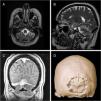

To report a case of post-surgical encephalocele through craniotomy burr holes following the resection of a meningioma of the posterior fossa. A 49-year-old female presented in the emergency room with cephalea. The MRI showed a meningioma of the convexity of the posterior fossa. A resection was performed and the bone flap replaced. The patient recovered uneventfully and was discharged. After 30 days the patient consulted referring cephalea, vomiting and imbalance. Brain MRI revealed a trans-cranial cerebellar herniation through the craniotomy burr holes. An urgent surgery was performed to repair the encephalocele. Post-surgical brain MRI was performed and did not show complications.

Post-surgical encephalocele is an uncommon complication after the resection of a posterior fossa lesion. To avoid this complication, it is recommended thorough dural and bony closure, particularly in the posterior fossa surgeries and in high-risk patients.